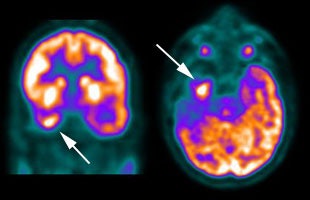

CNS recurrent glioma: The patient below had a history of a right temporal lobe glioma. The lesion had been treated with surgery and radiation. A follow-up MR exam demonstrated areas of enhancement in the right temporal lobe on post-gadolinium images (black arrows). MR spectroscopy was inconclusive. The FDG PET exam demonstrated a hypermetabolic focus in the area of MR signal abnormality consistent with recurrent glioma (white arrows). |

|